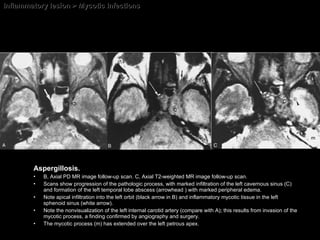

Mycotic Infections Mucormycosis There are four major types of mucormycosis:  rhinocerebral = M/C type pulmonary gastrointestinal disseminated

Mycotic Infections Rhinocerebral type of mucormycosis usually occur in DM or immunocompromised.  M/C = Mucor  and  Aspergillus. The infection usually begins in the nose Spreads to the paranasal sinuses Extends into the orbit and cavernous sinuses. The pathologic hallmark of mucormycosis = invasion of the walls of small vessels.  Rapid brain infarction may develop.

Mycotic Infections Imaging findings Combination of orbital and sinus involvement Multicentric or unicentric sinusitis  Mycetoma  = HypoSI on T2WI :  One important sign but not pathognomonic. vascular thrombosis Invasion of the walls vessels.

Inflammatory lesion > Mycotic Infections Aspergillosis. A, Axial T2WI shows soft-tissue induration in the left sphenoid sinus (white arrow).  Note the internal carotid (C) and early soft-tissue infiltration of the left cavernous sinus (hollow arrow).

Inflammatory lesion > Mycotic Infections Aspergillosis. B, Axial PD MR image follow-up scan. C, Axial T2-weighted MR image follow-up scan.  Scans show progression of the pathologic process, with marked infiltration of the left cavernous sinus (C) and formation of the left temporal lobe abscess (arrowhead ) with marked peripheral edema.  Note apical infiltration into the left orbit (black arrow in B) and inflammatory mycotic tissue in the left sphenoid sinus (white arrow).  Note the nonvisualization of the left internal carotid artery (compare with A); this results from invasion of the mycotic process, a finding confirmed by angiography and surgery.  The mycotic process (m) has extended over the left petrous apex.